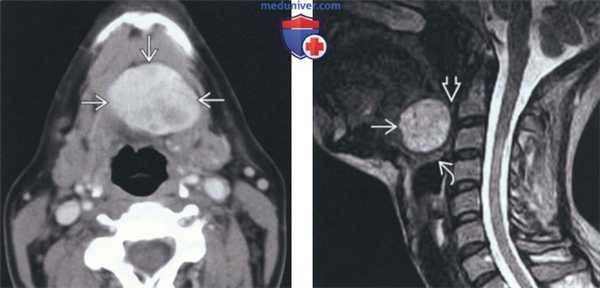

(Слева) КТ с КУ, аксиальная проекция. Подслизистое образование с четкими контурами, расположенное вдоль средней линии дна полости рта. Неоднородная плотность говорит о возникновении зоба.

(Справа) При МРТ Т1ВИ в сагиттальной проекции определяется неоднородное гиперинтенсивное образование, расположенное вдоль средней линии корня языка. Обратите внимание на сужение просвета ротоглотки, а также смещение надгортанника кзади и книзу.

(Слева) На аксиальной КТ с КУ в области дна по средней линии определяется объемное образование с четкими контурами, представленное эктопической тканью щитовидной железы неоднородной плотности (может быть сопоставимо с ранними изменениями при зобе).

(Справа) На сагиттальной MPT (STIR, срединный срез) в основании языка визуализируется объемное образование с неоднородным гиперинтенсивным сигналом, заполняющее валлекулу. В этом случае язычная щитовидная железа обусловливает значительное сужение просвета ротоглотки, смещая надгортанник кзади и книзу.